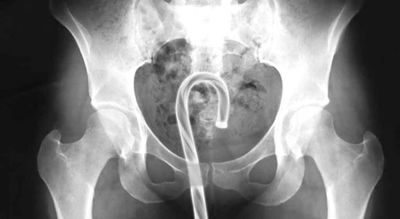

Emergency physicians consistently note that many cases become more complicated because patients attempt to resolve the problem themselves before seeking help. Imaging often reveals secondary objects, tweezers, coat hangers or other improvised tools, introduced during failed removal attempts. Clinicians warn that these efforts increase the risk of internal injury, bleeding and infection. The advice repeated across case studies is straightforward: early medical intervention is safer than improvisation.

Doctors note that objects without a flared base are particularly likely to become lodged, as suction can form once the item moves beyond reach.